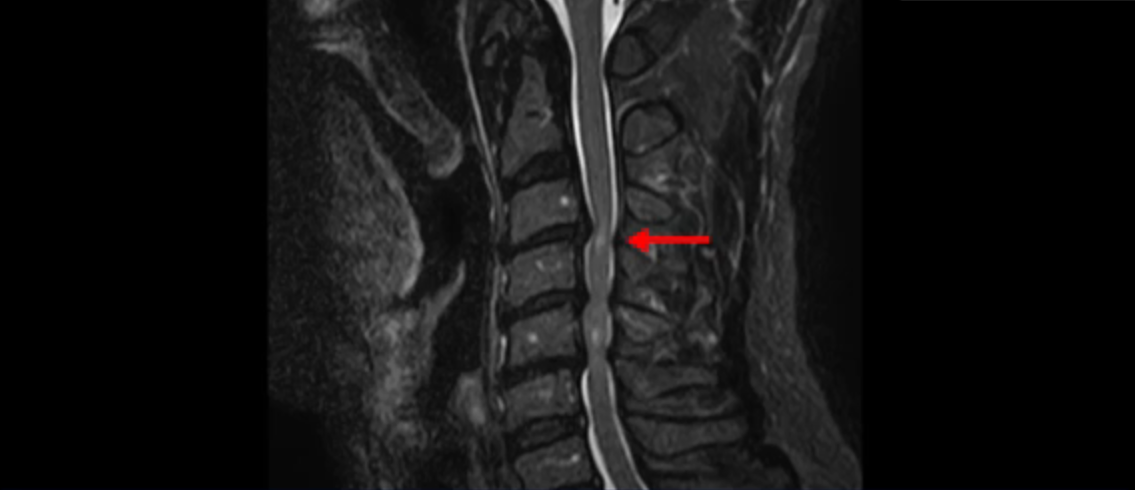

이 환자분은 목디스크 3, 4번의 심한 디스크로 인해 경추척수증이 발생한 환자입니다. MRI에서 보시다시피 심하게 밀려 나온 목 디스크로 인해 척수신경이 눌려서 신경이 손상된 게 하얗게 보입니다.

경추척수증은 중추신경인 척수가 목디스크, 골화된 후종인대, 경추 협착에 의해 심하게 눌려서 손상이 생기는 질환을 말합니다. 이 환자분의 증상은 목이 항상 담 걸린 듯 뻐근하고 걸을 때 발을 헛딛고 젓가락질이 잘 안되며 단추를 끼울 때 잘 안 껴지고 손에 잡은 물건이 자꾸 떨어지려고 하는 상태였습니다. 이와 같은 증상들은 전형적인 경추척수증의 증상입니다.